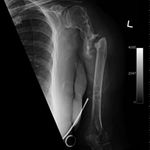

Some time in late May 2010, she presented with movement of the fracture site and was noted that the central area of healing had broken down and was thought that she had a deep infection. She was taken back to theater in mid June 2010 when operation showed that there was no pus. Multiple samples of the fracture site were taken and an external fixator applied with compression of the fragments. Following that, the cultures taken from the wounds showed no growth and no organisms and a biopsy showed no sign of any malignancy or abnormal cells. The fixator became loose and eventually had to be removed. This was done in July 2010 and she was discovered to be going onto a hypertrophic nonunion. Low dose ultrasound treatment of the fracture site was tried to help stimulate healing over the course of a few months but the non union persisted.

She was advised of the need to do some sort of stabilization which is necessary since the use of low-dose ultrasound has not helped in the healing process. She was unwilling to have any further operative intervention and sought further options. Eventually, she agreed to a fourth procedure of intra-medullary nail stabilization of the fracture and had this carried out in April 2011. An intramedullary nail was inserted in an antegrade manner and she has since gone on to heal the fracture site completely and has regained most of the function of the upper limb with no pain.